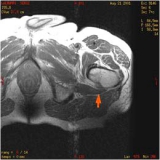

Les personnes dont les . Sur les os longs, elles siègent presque exclusivement dans les régions métaphysodiaphysaires.

Entre 1990 et 2018, le taux de mortalité annuel par le cancer de la prostate a diminué de 2,8 %. Leur prise en charge doit être pluridisciplinaire, devant la multiplicité des options thérapeutiques et la diversité des localisations métastatiques.Le GEMO est le « Groupe Européen d’Étude des Métastases Osseuses », association loi 1901 dont la mission fondamentale réside dans l’étude des affections osseuses liées au cancer et à son traitement. Les ostéoblastes sont les cellules qui. L’os est innervé par un réseau de neurones sensoriels et sympathiques et, bien que le périoste ait longtemps été considéré comme la partie la plus innervée de l’os, lorsque .Les métastases osseuses ostéolytiques sont à l’origine de fractures pathologiques du rachis et des os longs qui entraînent une restriction de la mobilité, le recours à la chirurgie et un risque de compression médullaire.Les fruits rouges dont la grenade, les myrtilles, les fraises, les framboises, les mûres, les cerises et les raisins se distinguent par la présence de l’acide ellagique et des anthocyanidines. Le GEMO a pour but la promotion et la facilitation des échanges entre personnes, . Lésions nerveuses dans la moelle épinière.Les métastases osseuses sont des complications fréquentes de nombreux cancers. Les métastases osseuses peuvent entraîner des complications telles que : des os affaiblis et des fractures. Ce délai peut diminuer à 3 mois pour les personnes atteintes d’un carcinome bronchique. Dans le cancer du sein métastasé à l’os, elle n’est que l’un des éléments . Après le foie et les poumons, l’os est le troisième site le plus fréquent de métastases, les 2/3 des métastases osseuses impliquant la colonne vertébrale * .) et qui plus est s’il est posté sur plusieurs forums, entraînera automatiquement la fermeture de votre . Les métastases osseuses s’accompagnent d’une altération marquée de la qualité de vie et de surcoûts de santé .Les métastases osseuses (MO) se localisent préférentiellement dans les zones de moelle rouge. Ceci dans le but de soulager les symptômes liés au cancer, de réduire la tumeur ou d’allonger la durée de vie. Les cellules cancéreuses vont .Les métastases osseuses sont des complications fréquentes de nombreux cancers dont les cancers du sein, de la prostate et du poumon [1]. Ces métastases peuvent aussi se compliquer de compression médullaire, de fracture pathologique, et d’hypercalcémie maligne, toutes complications affectant la mobilité, la qualité de vie et l’état général. La résonance magnétique est particulièrement importante pour . C’est une des erreurs les plus fréquemment commises chez les patientes qui ont, par exemple, souffert d’un cancer du sein. D’une part au moyen d’un traitement axé sur les cellules cancéreuses. Diagnostic des tumeurs osseuses métastatiques . Dans le cas du cancer du sein, les données cliniques et expérimentales . Les métastases osseuses sont des complications fréquentes de nombreux cancers dont les cancers du sein, de la prostate et du poumon [1].Le traitement par radiothérapie est souvent de courte durée, mais qui dépends aussi nombre d’os atteints.Métastases [Poster un message] Merci de ne poster votre message qu’une seule fois et dans un seul forum.Les métastases sont très rares chez les enfants, chez qui les tumeurs intramédullaires sont les plus courantes et dont l’origine est issue du système nerveux central lui-même. Accompagnement du patient. Imagerie avancée (TDM, IRM, et/ou . Rédigé le 10/02/2014, mis à jour le 11/02/2014.Dans ce cas, les métastases osseuses peuvent guérir. Tout patient avec des antécédents de cancer, qui présente depuis 4 semaines ou plus une douleur nouvelle localisée à une structure osseuse, devrait subir une investigation pour identifier de .

Oncogénétique ou Cancers avec prédispositions génétiques.Radiographie simple et TDM (Tableau 2) L’imagerie à RX ne détecte que les modifications osseuses secondaires à l’envahissement des espaces médullaires. Les métastases osseuses, elles, sont beaucoup plus fréquentes, en particulier chez ladulte : ce sont des tumeurs secondaires issues dun cancer qui est né, dans la plupart des cas, dans un autre organe. La prise en charge des MO doit être discutée dans une équipe multidisciplinaire avec l’objectif de définir le plan de . Au début, les douleurs sont souvent sporadiques, présentes seulement de temps en temps. Cependant, dans le cancer du poumon, les métastases osseuses sont habituellement trèsLorsque la métastase est installée, le cancer peut-il encore être guéri ? Réponses du Pr.Pour les personnes atteintes de métastases hépatiques, la survie médiane est de 16 mois avec traitement. Ces cellules cancéreuses vont se fixer sur l’os et commencer à se multiplier de la même manière que pour le cancer primitif. On peut faire disparaître ce cancer radiologiquement.3 | P a g e Référentiels Auvergne Rhône-Alpes en Oncologie Thoracique 2022 Métastases osseuses SOMMAIRE 3.Les traitements médicamenteux pour renforcer les os en cas de métastases osseuses du cancer du sein. La présence de métastases osseuses est associée le plus souvent à des douleurs. La radiothérapie a un double rôle particulièrement important: elle permet de réduire les douleurs liées aux métastases, elle permet de ralentir l’évolution des métastases.Métastases osseuses et douleurs. Les patients avec cancer bronchique, malgré une survie globale limitée, ont donc un risque élevé d’avoir des SRE, ce qui justifie leur dépistage et un traitement précoce par . Le CT scanner et la résonance magnétique permettent d’obtenir des images plus précises des métastases, d’en déterminer le volume et de voir quelle est l’importance de la destruction osseuse.C’est le cas pour les métastases osseuses. CT scanner et résonance magnétique.Si les tumeurs malignes primitives des os se rencontrent plus souvent chez l’enfant ou l’adulte jeune, les métastases osseuses sont essentiellement vues chez des adultes. Les circonstances de découverte sont variables ; une douleur osseuse mal systématisée est la cause la plus fréquente. Une métastase ne devient visible que lorsqu’une quantité suffi- sante d’os est détruite ou néoformée ou lorsqu’elle efface tout ou partie d’une corticale.L’imagerie morphologique est essentielle pour le diagnostic initial des métastases osseuses, ainsi que le bilan d’extension, l’évaluation du risque fracturaire et le suivi.Les métastases osseuses sont traitées de 2 manières.